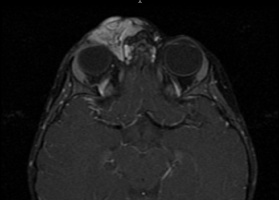

Although the diagnosis is clinical in cutaneous lesions, ultrasound should be used to image the extent of periorbital involvement. If deeper orbital extension is suspected, then CT or MRI may be used. On ultrasound, a capillary hemangioma shows high internal reflectivity with irregular acoustic structures. On CT, the lesion shows a low flow prominence with no disturbance of surrounding tissue and no bony erosion; it enhances with contrast. On Magnetic Resonance Imaging (MRI) studies, capillary hemangiomas may appear as well-circumscribed densely lobulated tumors. On T1-weighted MRI, the capillary hemangioma is of intermediate signal intensity, but it is moderately hyperintense on T2-weighted imaging (Figure 2) due to the slow blood flow through the vascular channels. The tumor mass may enhance following gadolinium contrast injection, so images should have fat suppression on T1 weighted images to better visualize the tumor. Angiography is rarely used as a diagnostic tool for capillary hemangiomas.